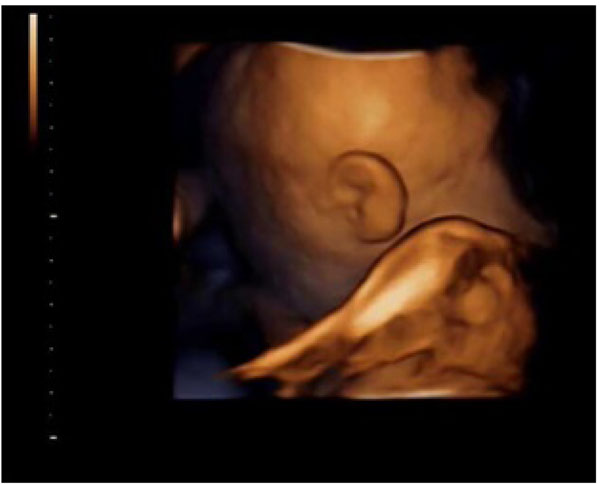

Fig. (3I). 4D Ultrasound Imaging of Fetal Face at the beginning of the test for a Group B Patient. Picture is unclear because face being blocked by artifacts and limbs.

Fig. (3II). Successful 4D Ultrasound Imaging of Fetal Face with clear facial features Post 30 minutes of walking in that same Group B patient as in picture 2. [I].